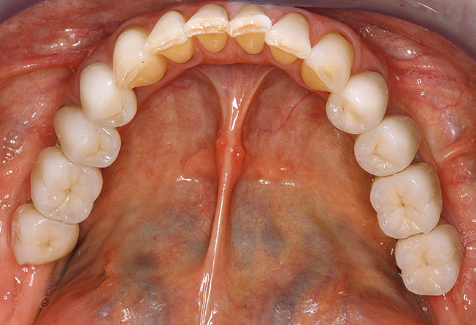

Fig. 9: Le superfici accessibili di impianti e denti sono lucidate con coppette da lucidatura e composti lucidanti adatti. - Fig. 10: Rispettare le istruzioni d'uso di ausili adeguati per l'igiene orale a casa dovrebbe far parte di SPT. - Fig. 11a eb: Situazione clinica 12 anni dopo l'inserimento del restauro protesico. Durante questo periodo, sono state osservate solo la rottura della ceramica del rivestimento estetico sul dente 47 e la necessità di un trattamento endodontico del dente 12. Tutti i restauri funzionano ancora come previsto.

Un'assistenza standardizzata e regolare a misura di rischio nell'ambito di SPT è la chiave per il successo del trattamento clinico a lungo termine nei pazienti con situazione periodontale compromessa. Ciò è particolarmente vero per i pazienti a cui vengono applicati impianti dopo il trattamento parodontale completato con successo (Fig. 11a e b).